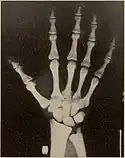

Pycnodysostosis causes the bones to be abnormally dense; the last bones of the fingers (the distal phalanges) to be unusually short; and delays the normal closure of the connections (sutures) of the skull bones in infancy, so that the "soft spot" (fontanelle) on top of the head remains widely open.[9] Because of the bone denseness, those with the syndrome suffer from fractures.[7]

Other abnormalities involve the head and face, teeth, collar bones, skin, and nails. The front and back of the head are prominent. Within the open sutures of the skull, there may be many small bones (called wormian bones). The midface is less full than usual. The nose is prominent. The jaw can be small. The palate is narrow and grooved. There will be delay in fall of milk teeth. The permanent teeth can also be slow to appear. The permanent teeth are commonly irregular and teeth may be missing (hypodontia). The collar bones are often underdeveloped and malformed. The nails are flat, grooved, and dysplastic. High bone density, Acro-osteolysis and obtuse mandibular angle are the characteristic radiological findings of this disorder.[10]

Pycnodysostosis also causes problems that may become evident with time. Aside from the broken bones, the distal phalanges and the collar bone can undergo slow progressive deterioration. Vertebral defects may permit the spine to curve laterally resulting in scoliosis. The dental problems often require orthodontic care and cavities are common.

- Hypoplasia or aplasia of the distal phalanges and ribs